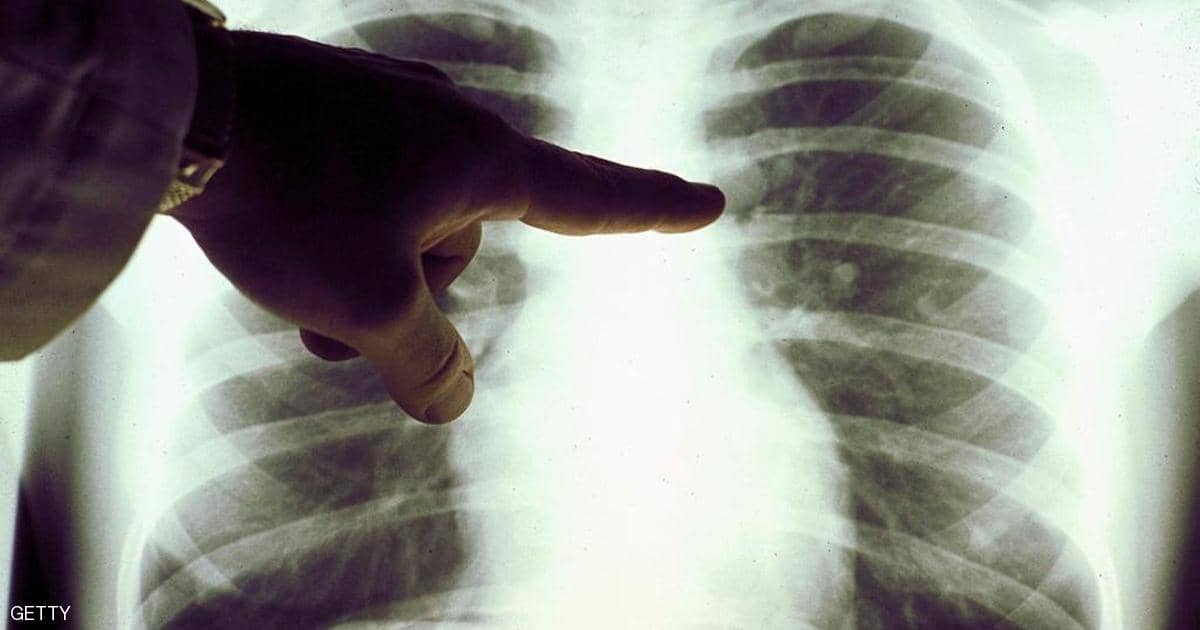

وتابع: “يبلغ المرضى، في البداية، عن ظهور أعراض أمراض الجهاز التنفسي ، مثل السعال وضيق التنفس وآلام في الصدر، قبل أن يتطور ذلك إلى أمراض مزمنة”.

وبلغ عدد الأشخاص الذين يعانون أمراضا رئوية خطيرة قد تكون مرتبطة بالسجائر الإلكترونية، 215 في 25 ولاية أميركية خلال 3 أيام فقط، حسبما كشف “سي دي سي”، الجمعة، فيما سُجلت حالة وفاة الأسبوع الماضي.